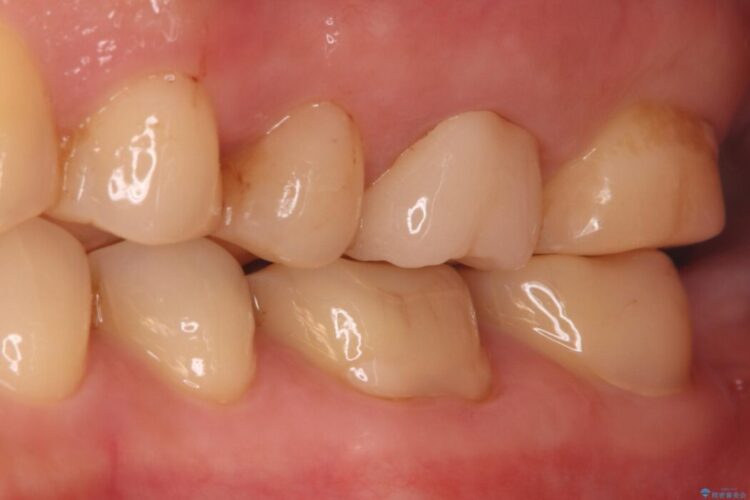

銀歯の段差の改善、ラバーダム防湿下で行うセラミックインレー治療

銀歯の段差の改善、ラバーダム防湿下で行うセラミックインレー治療 ビフォー 銀歯の段差の改善、ラバーダム防湿下で行うセラミックインレー治療 アフター

当院でメンテナンスに通われている患者様の症例です。